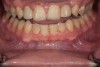

Fig 12. Prosthetic phase completion. Facial view. Note the more ideal horizontal overlap of anterior teeth and robust periodontal phenotype. Horizontal positioning of anterior teeth was enabled as a result of bone augmentation.

Figure 12